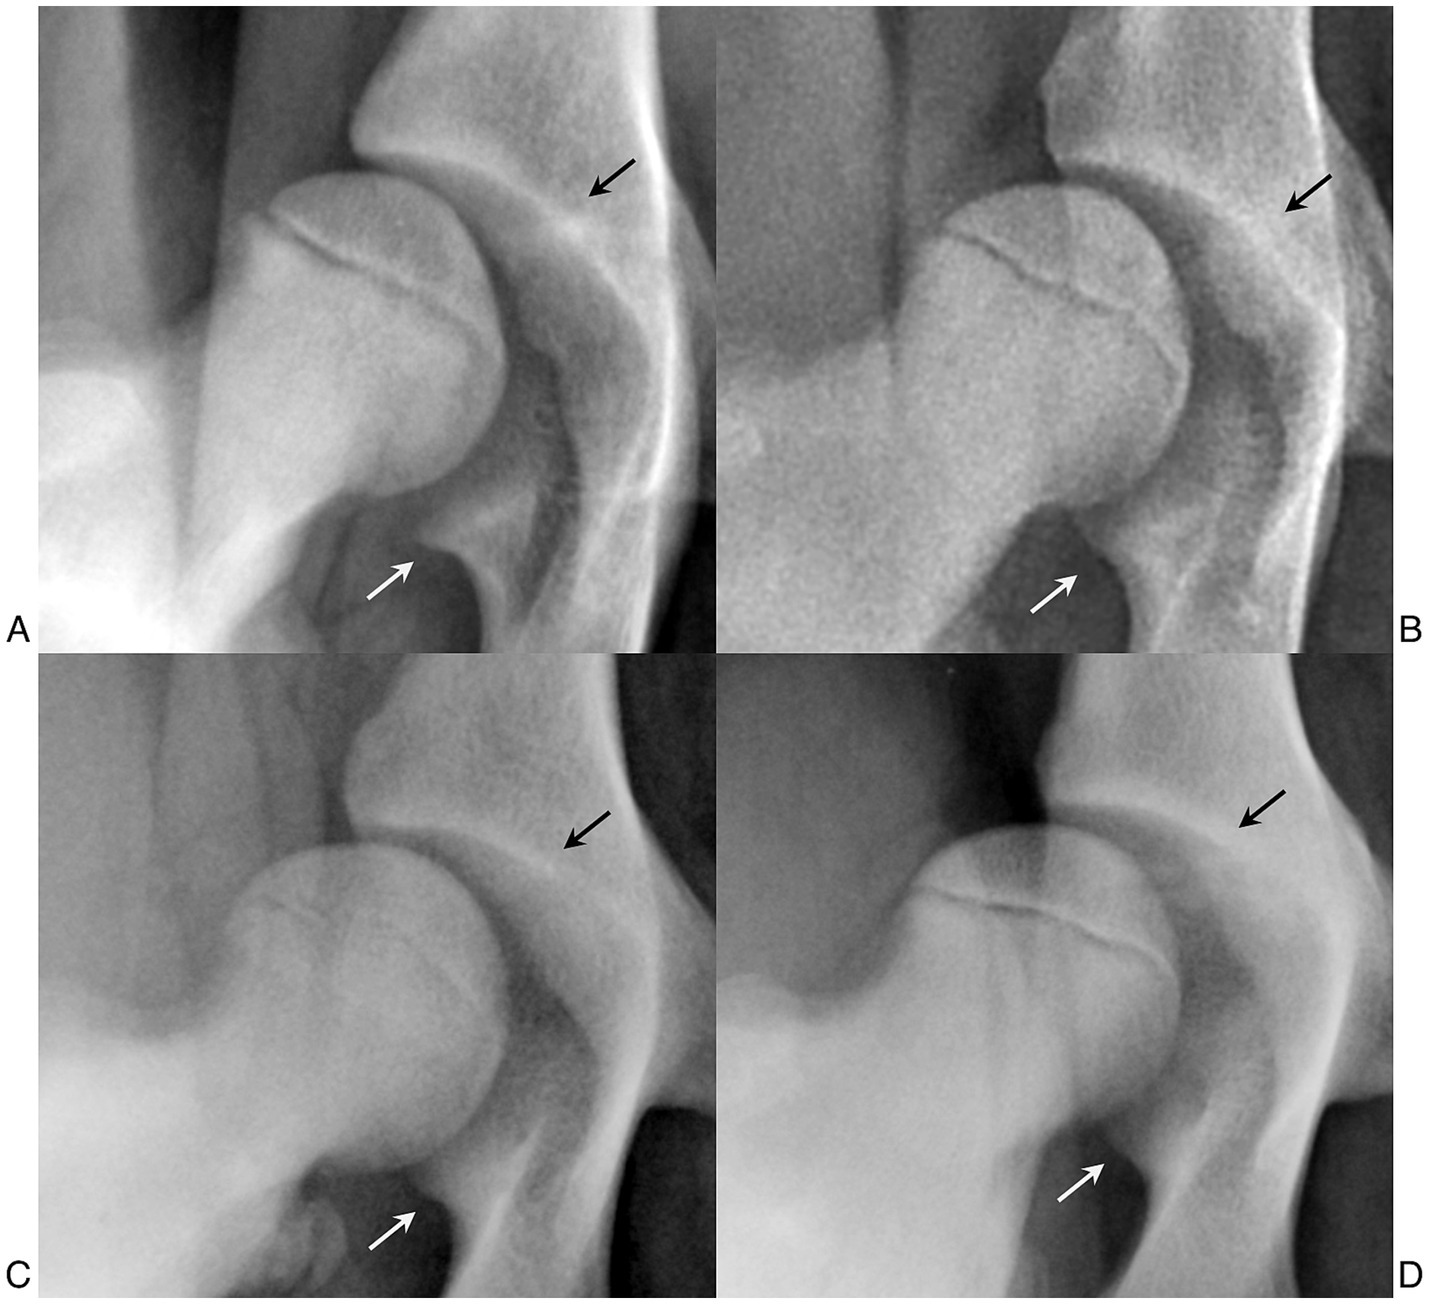

Introduction. The Vezzoni-Modified Badertscher Distension Device (VMBDD) technique is a radiographic method to assess hip joint laxity and is widely adopted in Europe. While the intra-observer and inter-observer variability of the Laxity Index (LI) measured on stress radiographs obtained with the VMBDD technique has been reported, it has never been evaluated in a large cohort of patients. The aim of our study is to assess the repeatability and reproducibility of the Laxity Index measured on stress radiographs obtained using the VMBDD technique in a large cohort of dogs. Methods. Stress-radiographs obtained with the VMBDD method of medium to large breed dogs, aged between 4.5 and 6 months, presented from 2021 to 2024 for screening of hip dysplasia were analyzed. The LI for each hip was blindly measured by three observers with different experience. Intra-and inter-observer significant variability was evaluated to assess repeatability and reproducibility of the LI, respectively. Statistical testing was performed and a p-value < 0.05 was considered significant. Inter-observer and intra-observer Intraclass Correlation Coefficients (ICCs) were evaluated. Results. One-hundred and ninety-five stress-radiographs (390 hip joints) were included. The inter-observer ICC showed moderate agreement (ICC = 0.55, 95% CI 0.50–0.59). EMMeans indicated that Observer 3 consistently provided higher LI values compared to Observers 1 and 2 across all time points (e.g., at T1: 0.484 vs 0.410 and 0.438, p-value < 0.001 for Observer 1 vs Observer 3). The repeatability within each observer were excellent for all three observers (Observer 1: ICC = 0.94, 95% CI 0.93–0.96; Observer 2: ICC = 0.99, 95% CI 0.99–0.99; Observer 3: ICC = 0.95, 95% CI 0.94–0.96). Conclusions. In-house evaluation of the LI on stress-radiographs obtained with the VMBDD technique was a high repeatable procedure, but it was a moderate reproducible measurement due to systematic upward bias by observer with less experience. Nevertheless, the mean differences could be negligible in a clinical setting due to the low impact on the definitive diagnosis.